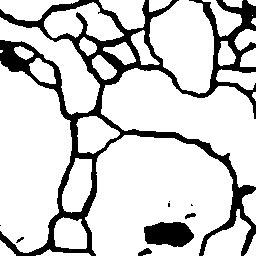

Vessel Extraction

Experiments are implemented on the Digital Retinal Images for Vessel Extraction database (DRIVE) proposed for studies on the extraction of blood vessels (Staal et al. 2004). Models are trained after reshaping all data at 256256 size. Rand score and information theoretic score is also used as evaluation metrics.

The following provides quantitative comparisons of three FCNs respectively. Example results on various image-to-image mapping tasks are shown in Figure 2.

Table 2 lists the best evaluation results. It shows that our model performs on par with U-Net and better than FCN-16s.